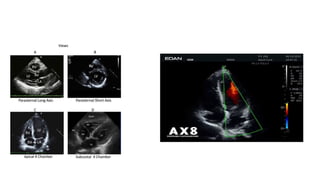

FOCUSED ASSESSED TRANSTHORACIC

ECHO(FATE)

• This approach basically involves four standardized acoustic views for

cardiopulmonary screening and monitoring.FATE was introduced by

Jensen et al for cardiopulmonary monitoring in the intensive care unit

• Focused cardiovascular ultrasound performed by anesthesiologists in

FOCUSED ASSESSED TRANSTHORACIC ECHO(FATE) •This approach basically involves four standardized acoustic views for cardiopulmonary screening and monitoring.FATE was introduced by Jensen et al for cardiopulmonary monitoring in the intensive care unit • Focused cardiovascular ultrasound performed by anesthesiologists in the perioperative period accurately detects major cardiac pathology and significantly alters perioperative management.